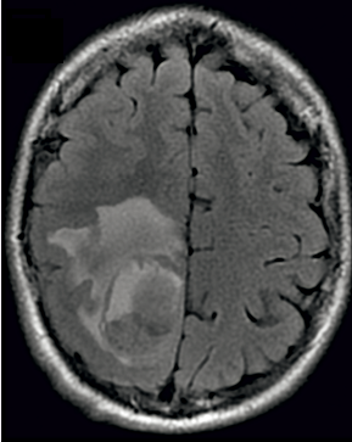

Ryc. 2. Ognisko udaru niedokrwiennego mózgu w prawym płacie potylicznym. Praca przedstawia przypadek 79-letniego mężczyzny, leczonego przewlekle z powodu niewydolności serca oraz cukrzycy typu 2. Pacjent zgłosił się do kliniki kardiologii z powodu zaburzeń świadomości. Kilka dni wcześniej chory został wypisany ze szpitala po epizodzie obrzęku płuc. W wyniku zastosowanego leczenia uzyskano stopniową poprawę stanu ogólnego. Podczas dalszej obserwacji szpitalnej doszło do ponownego pogorszenia kontaktu z chorym. Zdecydowano się na wykonanie badania tomografii komputerowej głowy, w którym uwidoczniono ognisko udaru niedokrwiennego mózgu w prawym płacie potylicznym. Pacjenta w trybie pilnym przekazano pod opiekę do kliniki neurologii.

The work presents the case of a 79-year-old man, chronically treated for heart failure and type 2 diabetes mellitus. The patient reported to the cardiology clinic due to consciousness disorders. A few days prior, the patient was discharged from the hospital after an episode of pulmonary edema. As a result of the employed treatment, the general condition gradually improved. During further hospital observation deterioration of contact with the patient reoccurred. The decision to perform a computer tomography of the head was made, which visualized a focus of ischemic stroke in the right occipital lobe. The patient was urgently transferred to a neurology clinic.